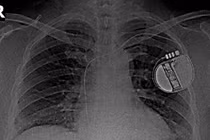

Nhịp tim đập quá nhanh kèm theo triệu chứng hồi hộp, thì nguy cơ cao đang gặp phải tình trạng rối loạn nhịp tim. Người bị rối loạn nhịp tim nếu không được điều trị sớm và đúng cách thì có nguy cơ gặp phải các biến chứng nguy hiểm.